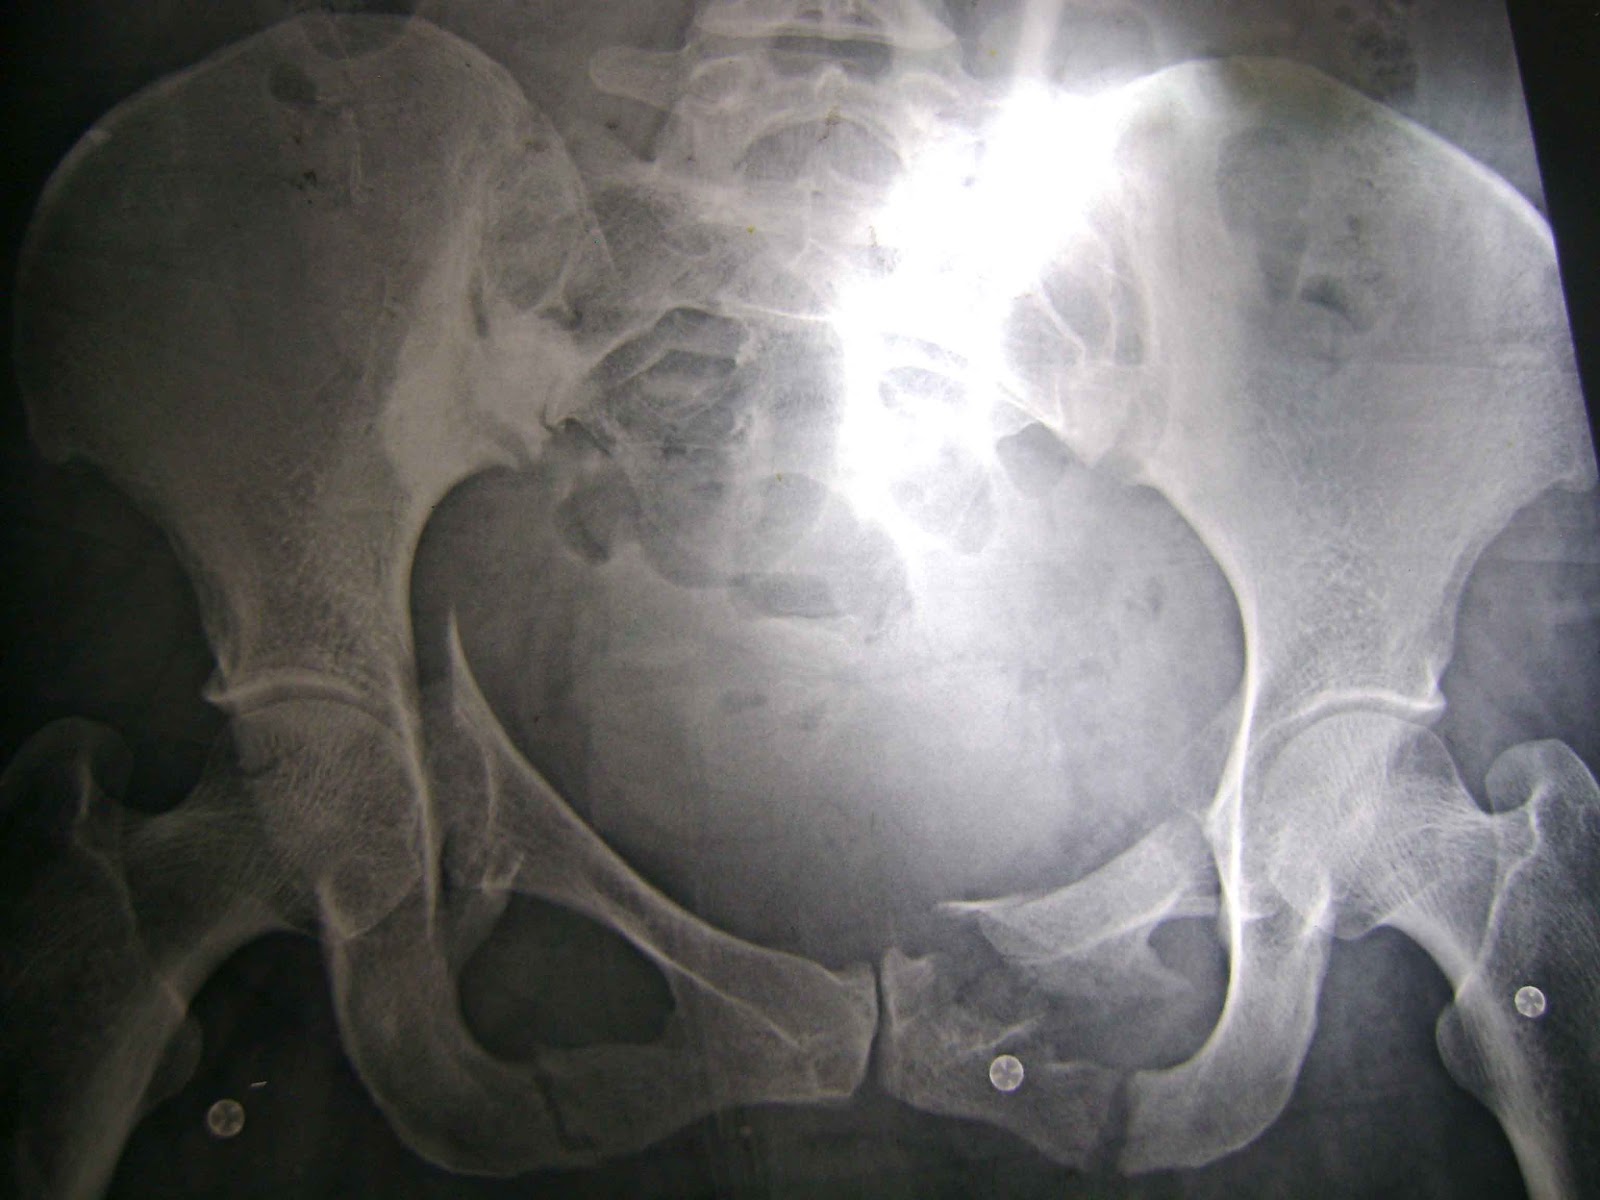

Cambio De Pañal En Paciente Con Fractura De Cadera. WebRealizamos el lavado y secado de los genitales de la misma manera que vimos en el cambio de pañal encamado. Colocamos a la altura de las rodilla de la. Webvertiginosa. En España se producen anualmente unas 30.000 fracturas de cadera que son más frecuentes en mujeres, debido a la elevada prevalencia de osteoporosis. Su.

WebEvaluar la incidencia de fractura de cadera en pacientes con tratamiento antipsicótico, comparándola con la de individuos que no han sido tratados con antipsicóticos. Diseño. WebDicha fractura, acaba derivando en problemas que van más allá del daño ortopédico, afectando a diversas áreas como medicina interna, rehabilitación,.